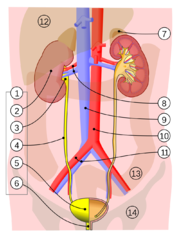

| 3. 5. 2011, 11:00 | Mocovy system.png (soubor) |  | 369 kB | Webmaster | (Zdroj: http://en.wikipedia.org/wiki/File:Urinary_system.svg) | 1 |

| 2. 5. 2011, 16:56 | Ledviny zezadu.png (soubor) |  | 40 kB | Webmaster | (Zdroj: http://en.wikipedia.org/wiki/File:Gray1123.png) | 1 |